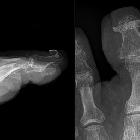

Nagelklammer

am Großzehennagel im Röntgenbild zur Anhebung der Nagelränder bei einwachsendem Nagel.